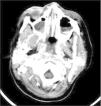

En la radiografía de tórax se detecta un derrame pleural bilateral. En la radiografía de senos se aprecia la ocupación parcial de senos maxilares. En la TC craneal se visualiza la ocupación de fosas nasales y senos paranasales, sin colecciones ni áreas flemonosas cervicales (fig. 2). En la biopsia de mucosa nasal y secreción de seno maxilar se detectan S. aureus y S. pneumoniae. La detección de Mucor y de Aspergillus es negativa. El hemocultivo resulta estéril. Las serologías para parvovirus, citomegalovirus y virus de Epstein-Barr son negativas. En la punción lumbar no se detectan alteraciones. Dada la llamativa pancitopenia, se realizan aspirado y biopsia de médula ósea.